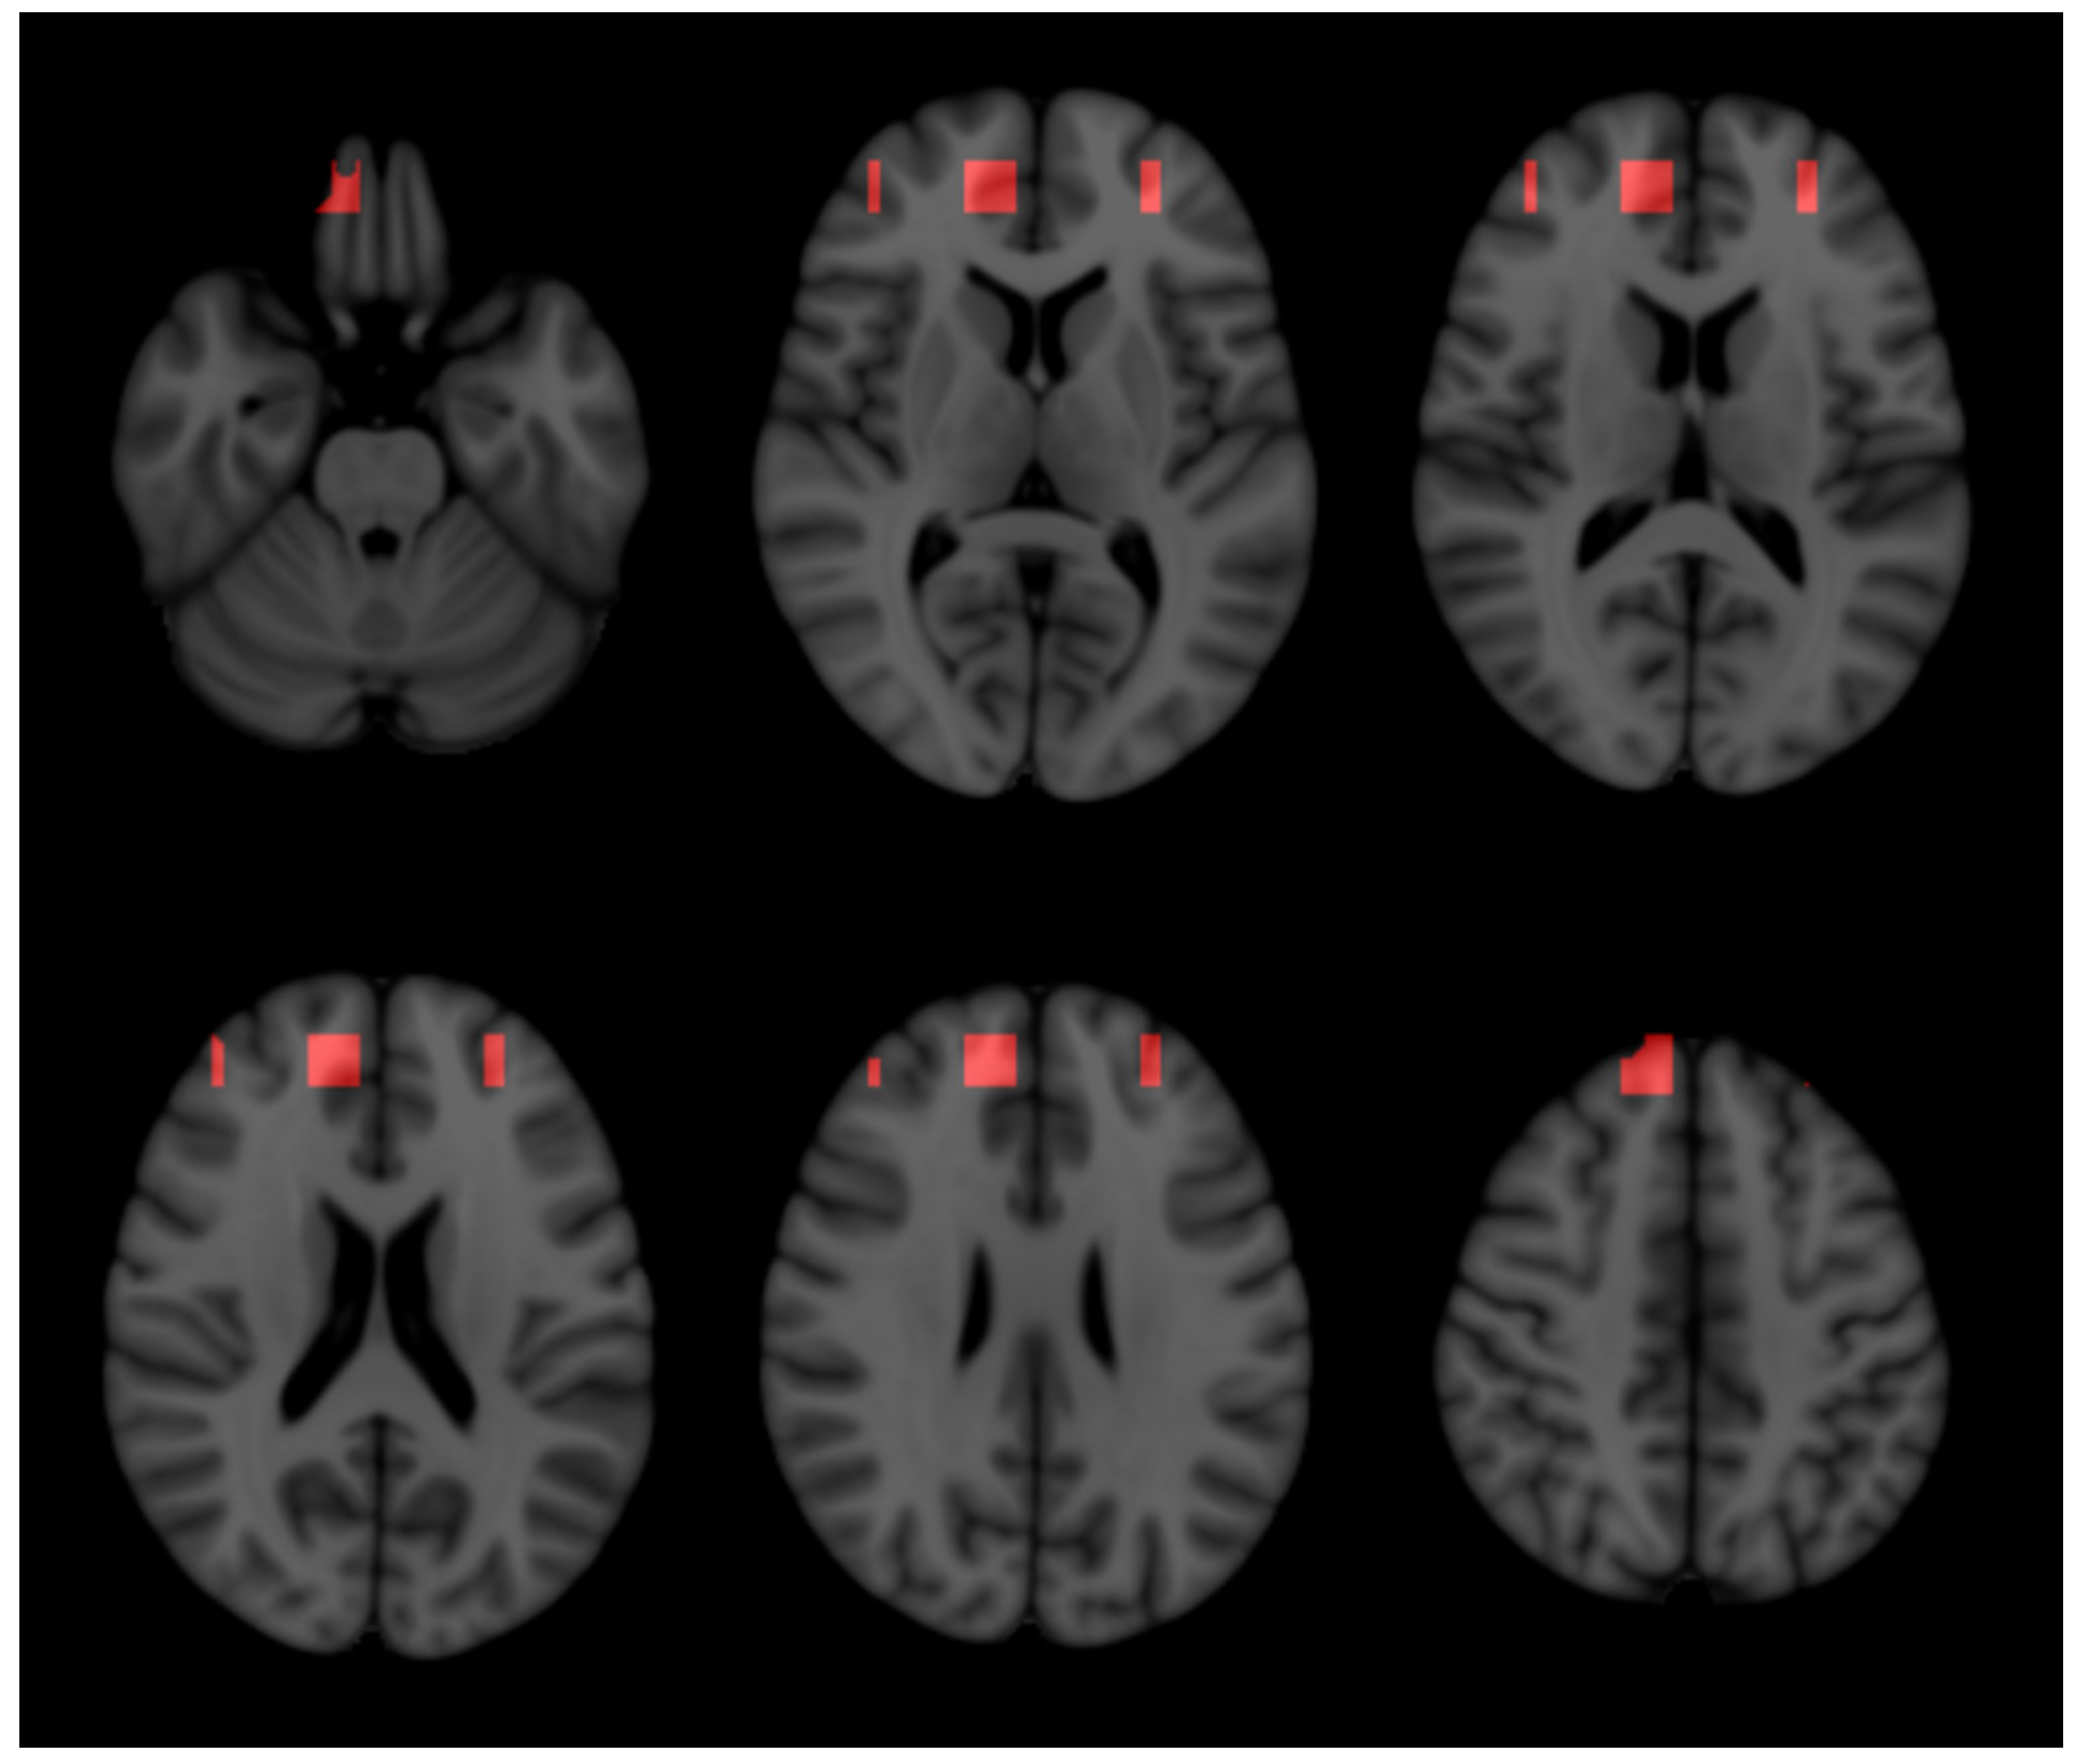

2.3. Three-Dimensional Representation

4.5.5. Three-Dimensional Representation